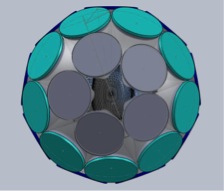

The third example of our current investigations is the development of a multi-detector-module multi-pinhole (MPH) SPECT brain-imaging system ideally suited for quantitative dynamic and high-spatial-resolution static SPECT imaging. Dynamic imaging will be enabled by obtaining sufficient angular sampling without the need for rotation. The system will automatically adapt its imaging characteristics (aperture size and number of pinholes open for imaging) in response to the imaging tasks and individual patients. It will thereby optimize lesion detection and quantification, as well as provide optimal data for pharmacokinetic analysis within structures throughout the brain. The prototype design for this system is illustrated in the following computer aided design (CAD) drawings. These investigations are funded by NIH grant R01-EB022521.

|

|

| Shown left is a frontal view and right is a view from behind of SolidWorks CAD renderings of the proposed prototype configuration of the 23 detectors of the system dedicated to brain SPECT imaging. Shown are detector modules with MPH aperture plates towards the brain and circular scintillation detector crystals opposed to them. | |